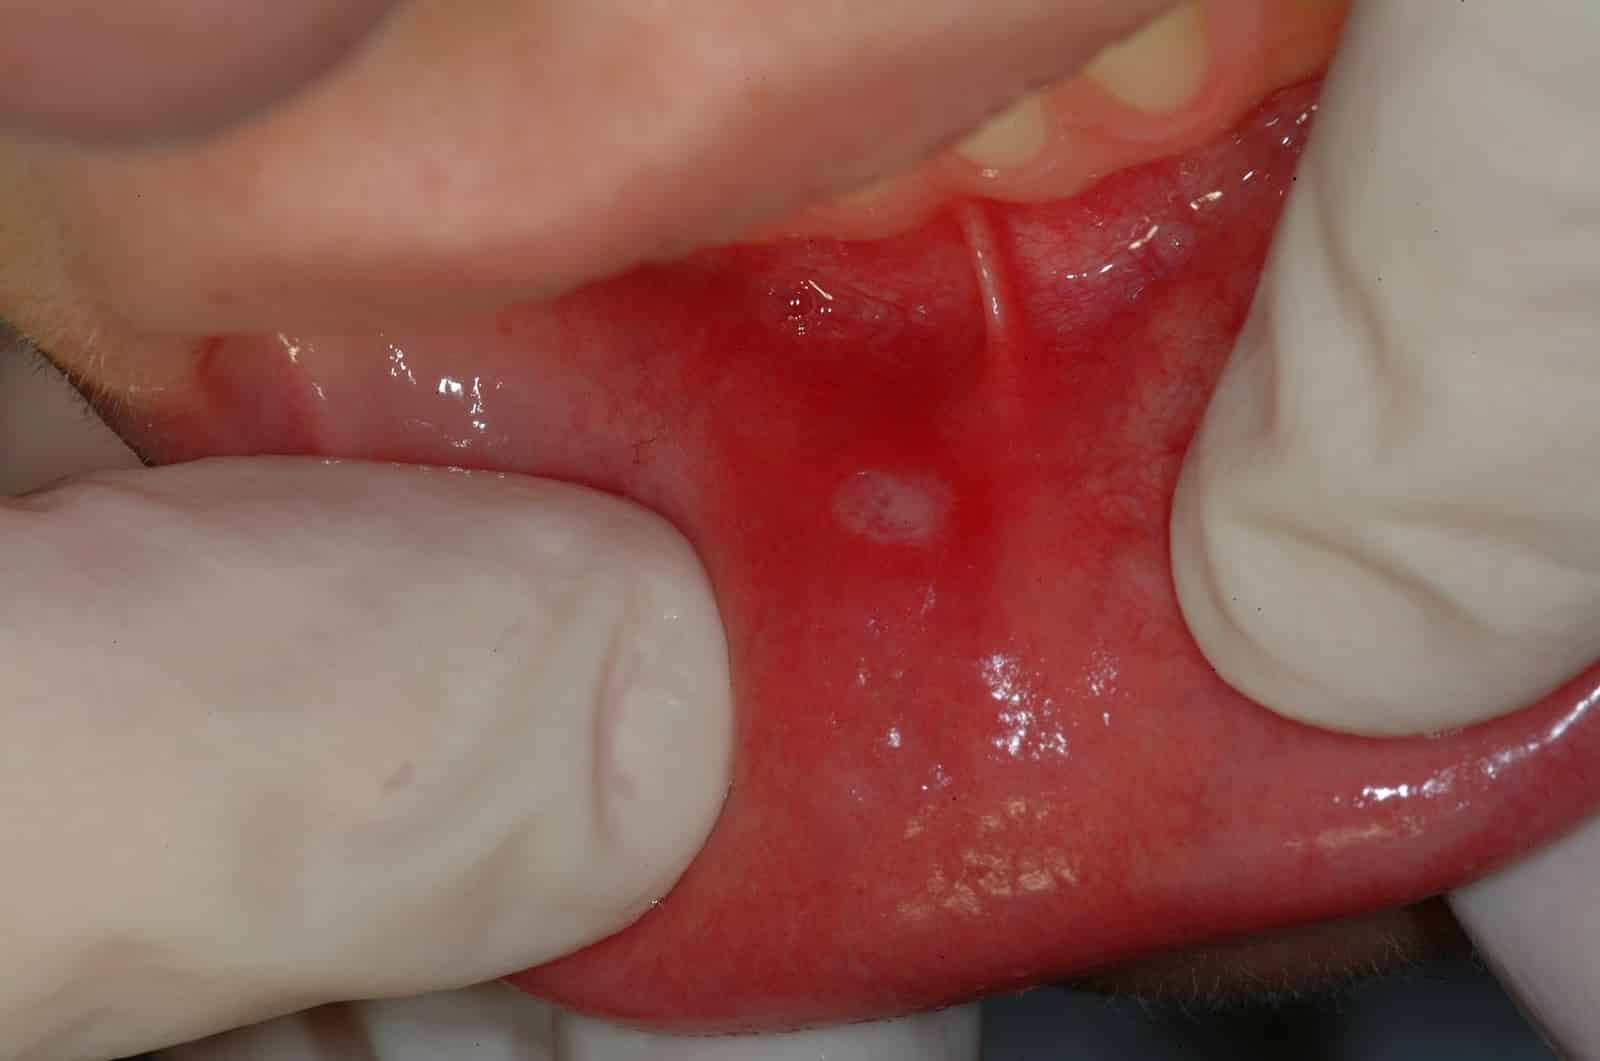

Кандидозный стоматит

Кандидозная форма стоматита встречается чаще у грудничков. Вызывают его грибы рода Candida, которые в норме присутствуют на слизистой здорового человека. Активный рост микроорганизмов провоцируется снижением защитных сил организма вследствие приема антибиотиков, длительной болезни, авитаминоза и т.д. Для взрослых этот вид стоматита практически не заразен, если они не пользуются с заболевшим одной посудой. У малышей иммунитет слабее, поэтому дети часто подвергаются заражению.

Как определить, что у крохи молочница (народное название кандидозного стоматита):

- Проявляется это состояние белым налетом на языке, внутренней поверхности щек, небе.

- Под налетом обнаруживаются покрасневшие ткани, появление крови. Возможна небольшая отечность и болезненность слизистой.

- Если стоматит не лечить, появляются трещинки и язвочки, налет становится плотнее, сверху немного желтеет.